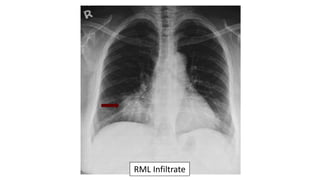

57 year old with cough

and shortness of

breath.

The CXR demonstrates:

a. Pulmonary edema

b. RLL pneumonia

c. RML pneumonia

d. Pulmonary embolus

e. Lung cancer

RML pneumonia:

ď‚§ Blurred right heart border

ď‚§ Lateral diaphragm clear

ď‚§ Often seen best on the lateral

RML Infiltrate